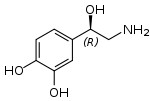

- Crack cocaine